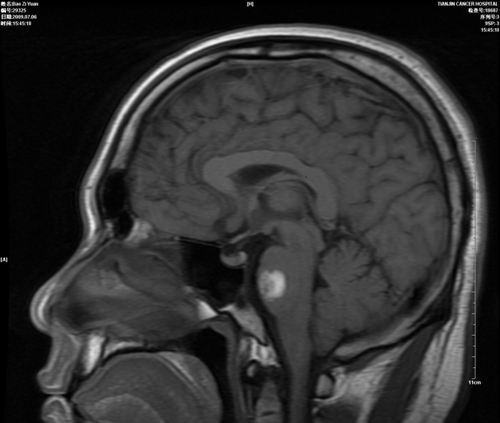

胶质瘤:

手术前